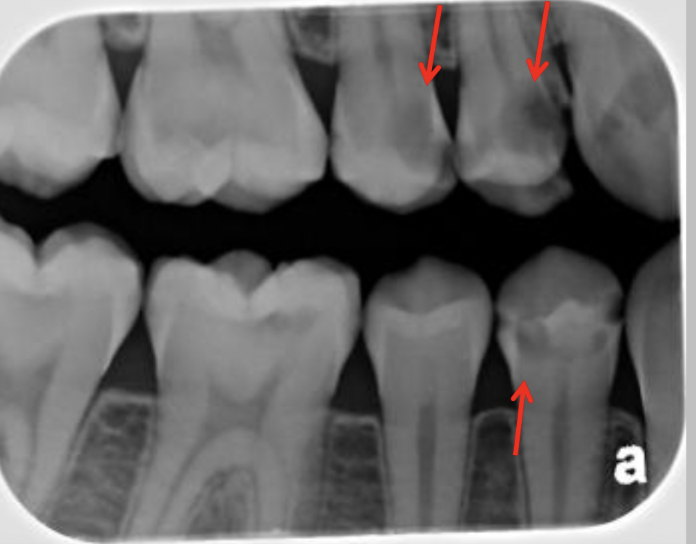

3

A

Initial caries (IC)

4

5

6

9

Classify the caries: